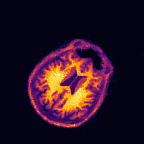

Multi-modality (or multi-channel) imaging is becoming increasingly important and more widely available, e.g. hyperspectral imaging in remote sensing, spectral CT in material sciences as well as multi-contrast MRI and PET-MR in medicine. Research in the last decades resulted in a plethora of mathematical methods to combine data from several modalities. State-of-the-art methods, often formulated as variational regularization, have shown to significantly improve image reconstruction both quantitatively and qualitatively. Almost all of these models rely on the assumption that the modalities are perfectly registered, which is not the case in most real world applications. We propose a variational framework which jointly performs reconstruction and registration, thereby overcoming this hurdle. Numerical results on simulated and real data show the potential of the proposed strategy for various applications in multi-contrast MRI, PET-MR, and hyperspectral imaging: typical misalignments between modalities such as rotations, translations, zooms can be effectively corrected during the reconstruction process. Therefore the proposed framework allows the robust exploitation of shared information across multiple modalities under real conditions.